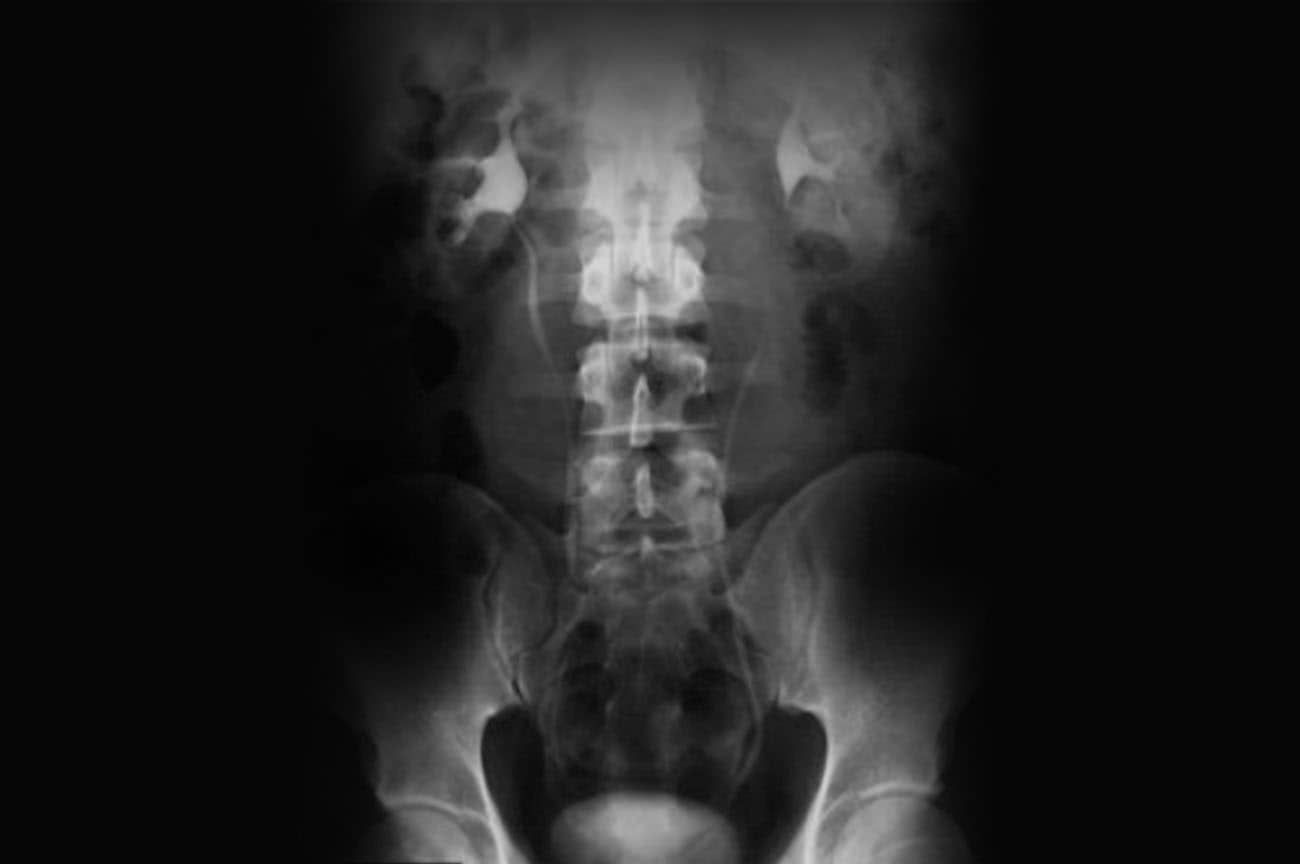

Incidência AP – Simples e séries da urografia excretora

Urografia excretora em AP – decúbito dorsal.

Urografia excretora em AP com contraste após 10 min.

Justificativa para realização do exame

Visualizar calcificações anormais que podem ser compatíveis com cálculos, hidronefroses, tumores ou infecções.

Principais estruturas demonstradas

Todo o sistema urinário, com exceção da uretra.

Fatores técnicos e posicionamento

• DFF: 1m.

• Tamanho do filme/receptor de imagem e sentido: 35x43cm no sentido longitudinal.

• Técnica de referência: 15mAs e 75KV, na mesa ou no seriógrafo.

• RC: perpendicular no centro do filme e ao nível das cristas ilíacas.

• Posição do paciente e da parte ou região do corpo: paciente em decúbito dorsal, com os braços ao lado do corpo, fornecendo um travesseiro e um suporte sob os joelhos para diminuir a tensão lombar.

• Respiração: parar a respiração e expor durante e expiração.

Atenção

Essa incidência radiológica serve para o primeiro exame do abdome, que é utilizado como referência para a série de exames complementares, cronometrados, geralmente, de 10 em 10 minutos, a critério do médico radiologista (condutor do exame). Esse exame também é conhecido como urografia intravenosa.